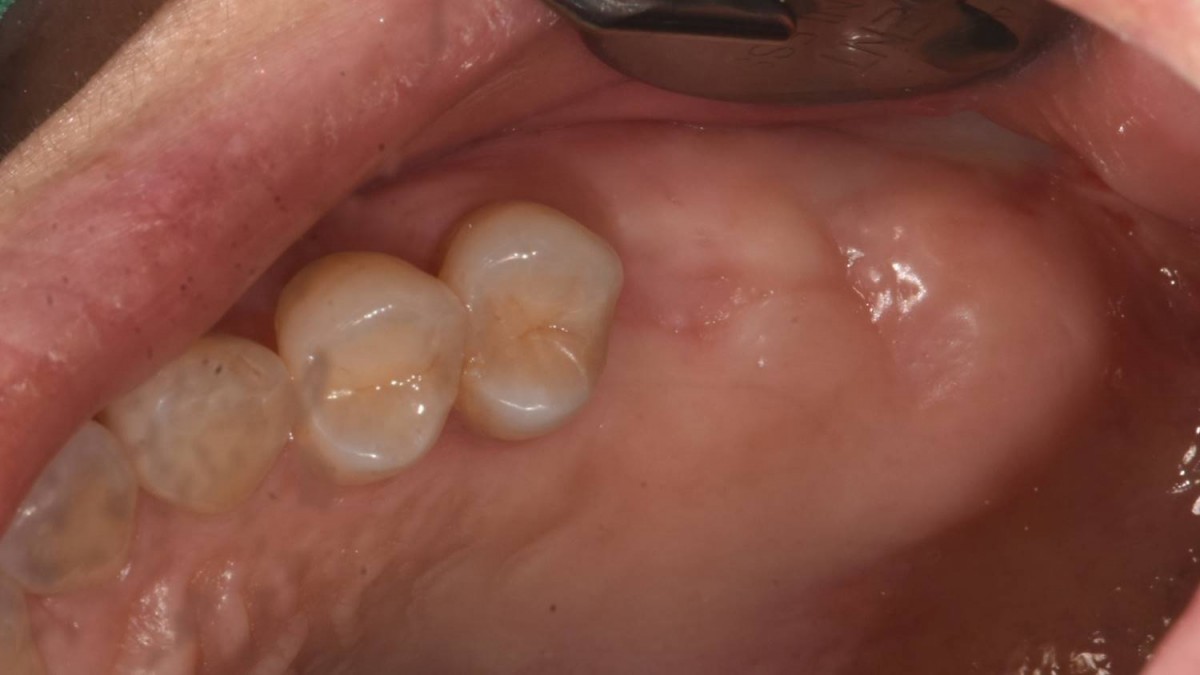

A 55-year-old female patient had

bilateral problems in both jaws.

It was decided to proceed with implant-supported restoration in the left molar part first.

▲Panoramic radiograph before the implant surgery in the lower left area.